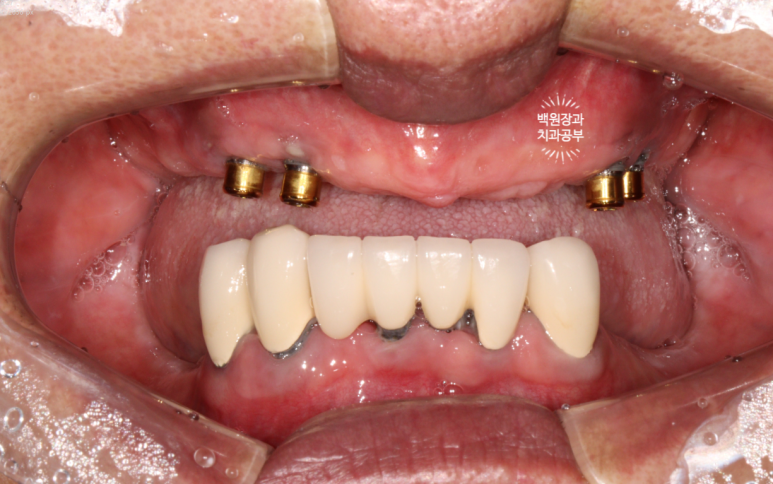

금색의 locator가 장착된 임플란트의 주변에 고름이 맺혀있는게 보이시나요..?

네개의 임플란트 모두 상당한 임플란트주위염에 시달리고 있는 것을 볼 수 있었습니다.

임플란트 주위 치주염에 걸려 고름이 나오면서 빠지기 직전이었던 위턱 임플란트 4개는 모두 제거하였고,

치아우식증과 치주염에 이환된 아래 치아들도 모두 발치하고, 2개의 임플란트를 새로 심어드렸습니다.!!!